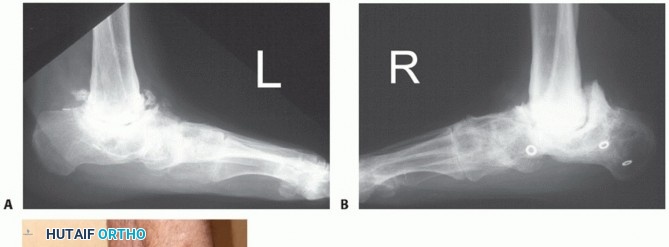

An ankle series of radiographs will reveal the extent of the bone loss, the extent of AVN, and the location of internal fixation hardware in the talus and plafond (FIG 3).

FIG 3 • A,B. Anterior and lateral x-ray of ankle with infected nonunion of talus. The ankle had a draining sinus. The talar body is avascular and the talar head has bone lysis around the two fixation screws. The plafond has erosion and destruction of the cartilage. There is reactive bone on the medial malleolus compatible with infection.*